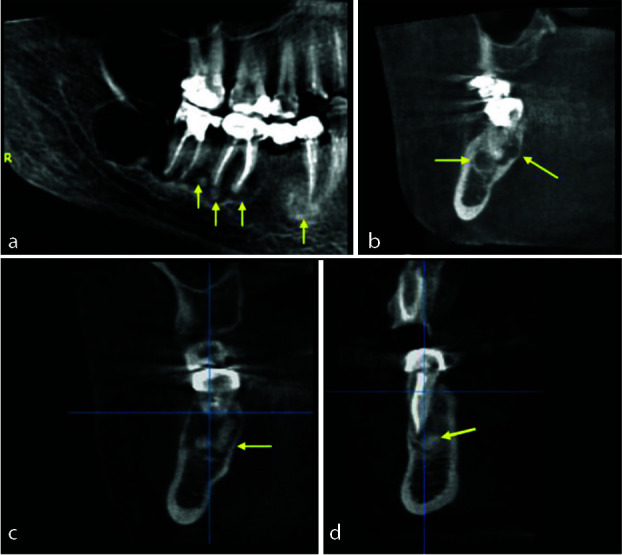

Cemento-osseous dysplasia (COD) is classified, by the World Health Organization as a benign fibro-osseous lesion related to the tooth and periapical area of the jaws and is considered as a benign reactive process appearing from the apical periodontium in close relation with the apices of teeth. Usually, it is asymptomatic, discovered accidentally, and affecting particularly middle-aged African women. There are four subtypes distinguished of the lesion: periapical (PCOD), focal (FCOD), florid (FLCOD) and familial florid cemento-osseous dysplasia (FFLCOD). Pseudocysts found in the jaws go by various names, including solitary bone cyst, traumatic bone cyst, or simple bone cyst (SBC). These two pathologies have been reported separately; however, their co-occurrence remains rare and the first case of FLCOD with co-occurrence of SBC was reported by Melrose et al. in 1976 and later a few cases been reported in the literature. The aim of this report is to describe a case of a 46-year-old oriental female diagnosed with FLCOD with co-occurrence of SBC. Under local analgesia, a surgical exploration of the cyst was performed. In addition, a biopsy with a trephine was done in the region of missing right first mandibular molar. Based on the patient clinical, radiographic, and histological findings, a diagnosis of FLCOD was made in co-occurrence with a mandibular SBC. An examination of another female family member unveils a distinctive case, and the familial factor has been ruled out. No further treatment was planned and only follow-up was suggested.

根据世界卫生组织的分类,牙骨质发育不良(COD)是一种与牙齿和颌骨根尖周围有关的良性纤维骨病变,被认为是一种良性反应性过程,出现在与牙齿根尖密切相关的根尖牙周。它通常无症状,偶然发现,主要影响中年非洲妇女。这种病变可分为四种亚型:根尖周型(PCOD)、局灶型(FCOD)、花斑型(FLCOD)和家族性花斑牙骨质发育不良型(FFLCOD)。颌骨中发现的假性囊肿有多种名称,包括单发性骨囊肿、创伤性骨囊肿或单纯性骨囊肿(SBC)。1976年,Melrose等人报告了第一例同时伴有SBC的FLCOD病例,后来又有一些病例在文献中出现。本报告旨在描述一例被诊断为 FLCOD 并发 SBC 的 46 岁东方女性病例。在局部镇痛的情况下,对囊肿进行了手术探查。此外,还在右下颌第一臼齿缺失区域进行了穿刺活检。根据患者的临床、影像学和组织学检查结果,诊断为下颌SBC同时伴有FLCOD。对另一名女性家庭成员的检查发现了一个独特的病例,并排除了家族因素。没有进一步的治疗计划,只建议进行随访。